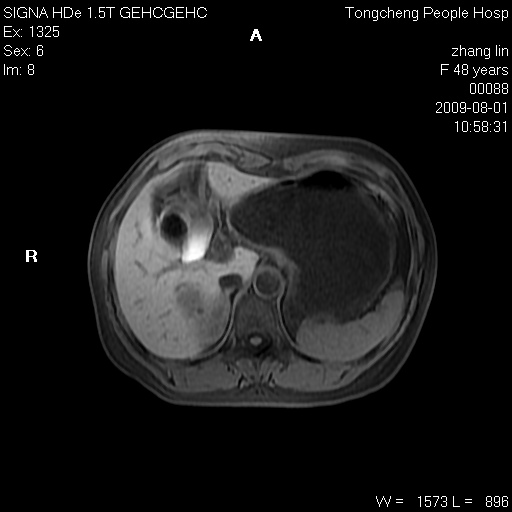

女,48岁。健康体检,彩超发现右肾占位性病变。平素健康。

临床诊断:右肾占位性病变,性质待定(囊肿?肿瘤?)。

上中腹部mr平扫+增强扫描,图像如下:

右肾上极见一类圆形病灶,t1wi呈等信号t2wi呈等高混杂信号,三期增强无强化,边界清---考虑囊肿出血。

同反相位均表现为等信号,病变无强化,考虑含蛋白的囊肿可能,弥散加权相或许有些帮助,

肝囊肿

慢性胆囊炎